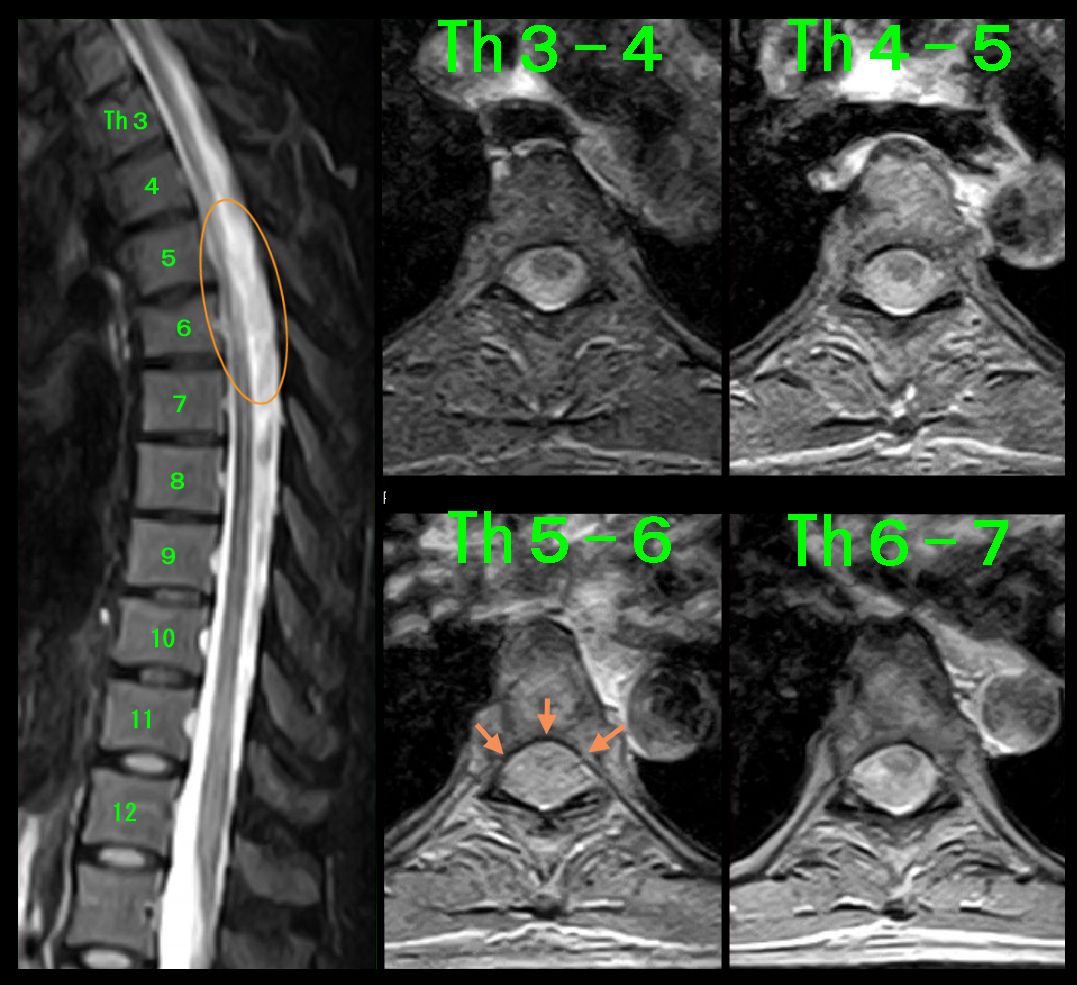

頚椎に異常が確認されなかったため、続けて胸椎のMRI検査を行いましたが、はオレンジ丸領域の脊髄が明瞭に描出されていないと評価しました。脊椎の後ろに脊髄がありますが、縦に走る黒い部分が脊髄で、脊髄は硬膜という袋に入っていて、硬膜の中を髄液という水が流れています。縦縞のストライプで白い部分が髄液となります。

MRDW.jpg

脊髄を横に切った画像が右側に並ぶ4断面となりますが、脊髄は目玉のように見えるのですが、Th5-6高位では黒目と白目が描出されていません。私はこれを脊髄が浮腫を起こした(腫れた)状態と理解していて、この脊髄の浮腫が背中の苦しさの原因と推察しました。

Th5-6高位で脊髄の浮腫と評価したぼやけた白黒のストライプも明瞭となり、脊髄の目玉の模様は一応黒目が確認される状態に改善したと評価できます。